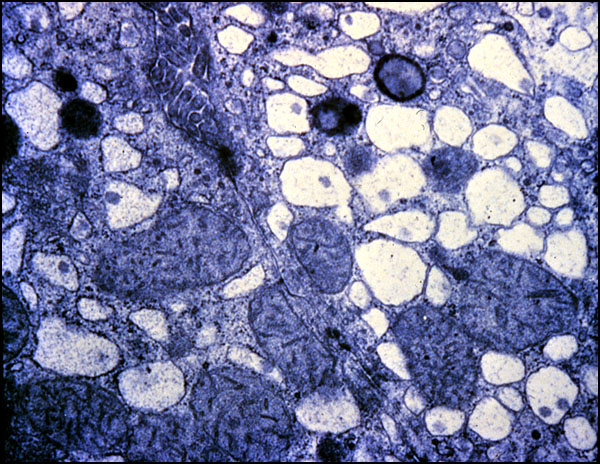

Vacuolar change

This EM photograph shows dilatation of the cisternae of rough endoplasmic reticulum (RER). There are no ribosomes attached to the RER which is indicative of "degranulation of RER". The dilated cisternae contain water which cannot be seen since it does not stain with osmium (the "EM stain").